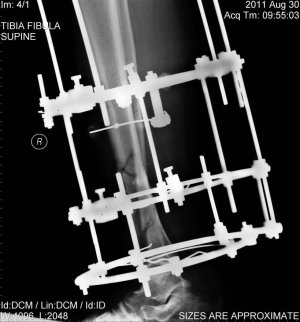

Возник вопрос об упражнениях для реабилитации после перелома голени и пятки (реабилитолог поликлиники сейчас в отпуске). Перелом произошел 3 месяца назад, наложение аппарата Илизарова осуществлено на неделю позже.

На данный момент могу поднимать стопу на 1 см максимум со слабым усилием, также создавать небольшое на опускание стопы. Пальцы но могу опускать (вжимать) нормально, но принципиально не могу поднимать (разжимать). Опухлость верхней части стопы держится все 3 месяца.